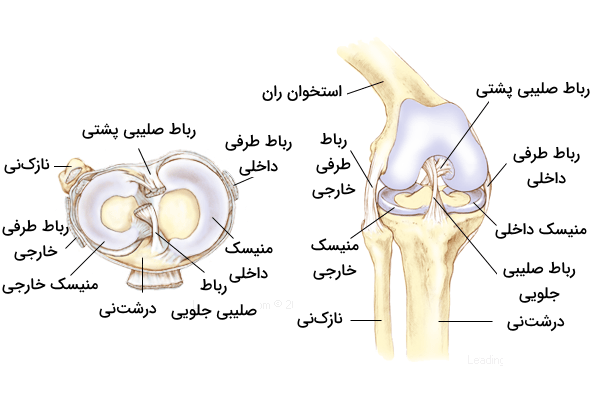

آناتومی رباطهای زانو

با بررسی آناتومی زانو متوجه میشویم که رباطهای مفصل زانو به دو دسته تقسیم میشوند که آنها را با عنوانهای زیر میشناسیم.

- «رباطهای خارج کپسولی» (Extracapsular Ligaments)

- «رباطهای داخل کپسولی» (Intracapsular Ligaments)

این رباطها ضمن متصل کردن فمور یا استخوان ران را به تیبیا یا درشتنی ، آن ها را در جای خود نگه میدارند و از جابهجا شدن موقعیت مکانی این استخوانها جلوگیری میکنند، بنابراین میتوان گفت حفظ ثبات مفصل زانو برعهده رباطها است. رباطهای خارجکپسولی در بخش خارجی کپسول مفصل دیده میشوند و شامل رباطهای زیر هستند.

- «رباط کشککی» (Patellar Ligament)

- «رباط طرفی خارجی» (Lateral collateral Ligament | LCL)

- «رباط طرفی داخلی» (Medial collateral Ligaments | MCL)

- «رباط پوپلیتئال مایل» (Oblique popliteal Ligament)

- «رباط پوپلیتئال قوسی» (Arcuate popliteal Ligament)

رباطهای داخل کپسولی در بخش داخلی کپسول مفصلی قرار دارند و معروفترین آنها «رباطهای صلیبی» (Cruciate Ligaments) هستند. در ادامه با هر یک از این رباطها در بخشهایی مجزا بیشتر آشنا میشویم.

اصلیترین رباطهای زانو

رباط طرفی خارجی

رباط طرفی خارجی یا رباط فیبولار جانبی، رباطی قوی است که از اپیکوندیل جانبی استخوان ران منشأ گرفته است. این رباط به سمت پایین حرکت میکند تا به سطح جانبی سر استخوان نازکنی یا «فیبولا» (Fibula) متصل شود.

رباط طرفی داخلی

رباط طرفی داخلی یا رباط جانبی داخلی، رباطی قوی و تخت در بخش داخلی مفصل زانو است. این رباط همراه با رباط طرفی خارجی فعالیتی مشترک با هدف تثبیت مفصل زانو و جلوگیری از حرکت جانبی بیش از حد دارند. این رباطها برای محدودسازی حرکت جانبی زانو، چرخش خارجی و داخلی زانو را در حالت کشیده محدود میکنند و به این ترتیب مطمئن میشوند که زانو آسیبی نبیند. این رباط را گاهی به دو بخش سطحی و عمقی تقسیم میکنند که در ادامه با ویژگیهای هر بخش آشنا میشویم.

رباطهای صلیبی

رباطهای صلیبی زانو در حقیقت دو رباطی هستند که به صورت اُریب از یکدیگر عبور میکنند و به همین دلیل به صورت یک صلیب یا حرف «X» انگلیسی، در درون مفصل به نظر میآیند. با وجود آن که تقاطع این دو رباط در درون کپسول مفصلی است، آنها وارد حفره سینوویال نمیشوند و در خارج از آن قرار دارند. هر یک از این دو رباط صلیبی را با نامی به خصوص میشناسیم که در ادامه با آنها آشنا میشویم.

- «رباط صلیبی جلویی» (Anterior Cruciate Ligament | ACL)

- «رباط صلیبی پشتی» (Posterior Cruciate Ligament | PCL)

در ادامه بخشهایی مجزا را به این دو رباط درونی زانو اختصاص میدهیم تا با نکات مرتبط با آنها بهتر آشنا شویم.

منیسکهای زانو

منیسکهای زانو صفحاتی هلالی شکل از جنس «فیبروکارتلاژین» (Fibrocartilaginous) هستند که در سطوح مفصلی فمور و تیبیا (استخوان ران و درشتنی) وجود دارند. منیسکها دو نقش بسیار مهم برعهده دارند.

- ایجاد تطابق یا همنهشتی بین دو سطح مفصلی: این عمل باعث افزایش ثبات و پایداری مفصل زانو میشود.

- ضربهگیری: منیسکها با افزایش ناحیه سطح تماس، نیروهایی که از طریق مفصل منتقل میشوند را پخش میکند و به این ترتیب فشار وارد شده کاهش مییابد.

در زانو دو منیسک داخلی و خارجی وجود دارد که هر دو آنها به انتهای ناحیه بین کوندیلی استخوان درشت نی متصل هستند. منیسک داخلی اتصالات دیگری نیز دارد که به شرح زیر هستند.

- اتصال به «رباط طرفی خارجی» (Medial Collateral Ligament)

- اتصال به کپسول مفصل

بنابراین اتصال بین منیسک داخلی و رباط طرفی خارجی، دلیل پارگی منیسک داخلی پس از وارد شدن آسیب به رباط طرفی خارجی است. منیسک خارجی که کوچکتر از منیسک داخلی است، به دلیل نداشتن هیچ اتصال اضافی، تحرک بیشتری دارد. به طور کلی باید گفت که حفظ موقعیت منیسکها و نگهداری آنها بر عهده چندین رباط است که در ادامه با آنها آشنا میشویم.

منیسک داخلی زانو

«منیسک داخلی» (Medial Meniscus) صفحهای فیبروغضروفی با ظاهری هلالی (مشابه با حرف C انگلیسی) و نیمدایرهای است که روی سطح صفحه تیبیای داخلی قرار گرفته است. شاخ جلویی منیسک داخلی به ناحیه بین کوندیلی جلویی درشتنی متصل است و به رباط صلیبی جلویی میپیوندد. شاخ پشتی نیز به ناحیه بین کوندیلی پشتی درشتنی، بین اتصالات منیسک خارجی و رباط صلیبی پشتی، متصل است.

منیسک خارجی زانو

«منیسک خارجی» (Lateral Meniscus) صفحهای فیبروغضروفی و به نسبت دایرهای است که سطح صفحه تیبیای خارجی را میپوشاند. شاخ جلویی این منیسک نیز، مشابه با منیسک داخلی، به ناحیه بین کوندیلی جلویی درشتنی متصل است، اما منیسک خارجی به طور کامل به رباط صلیبی جلویی نمیپیوندد و تا حدی با آن ترکیب میشود. ناحیه پشتی منیسک خارجی به ناحیه بین کوندیلی پشتی در بخش جلویی شاخ پشتی منیسک داخلی متصل است.